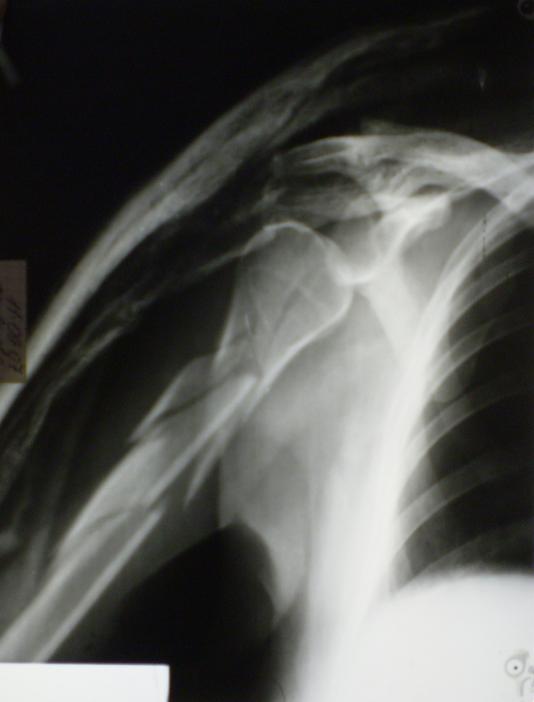

[Ortho] Многооскольчатый перелом плечевой кости в В/3

Брейса у нас нет. Повязку снял, обезболил и немножко исправил дефомацию,

положение небольшого отведения, повязка до здоровой лопатки с хорошей

протежеровкой. Вот что получилось.